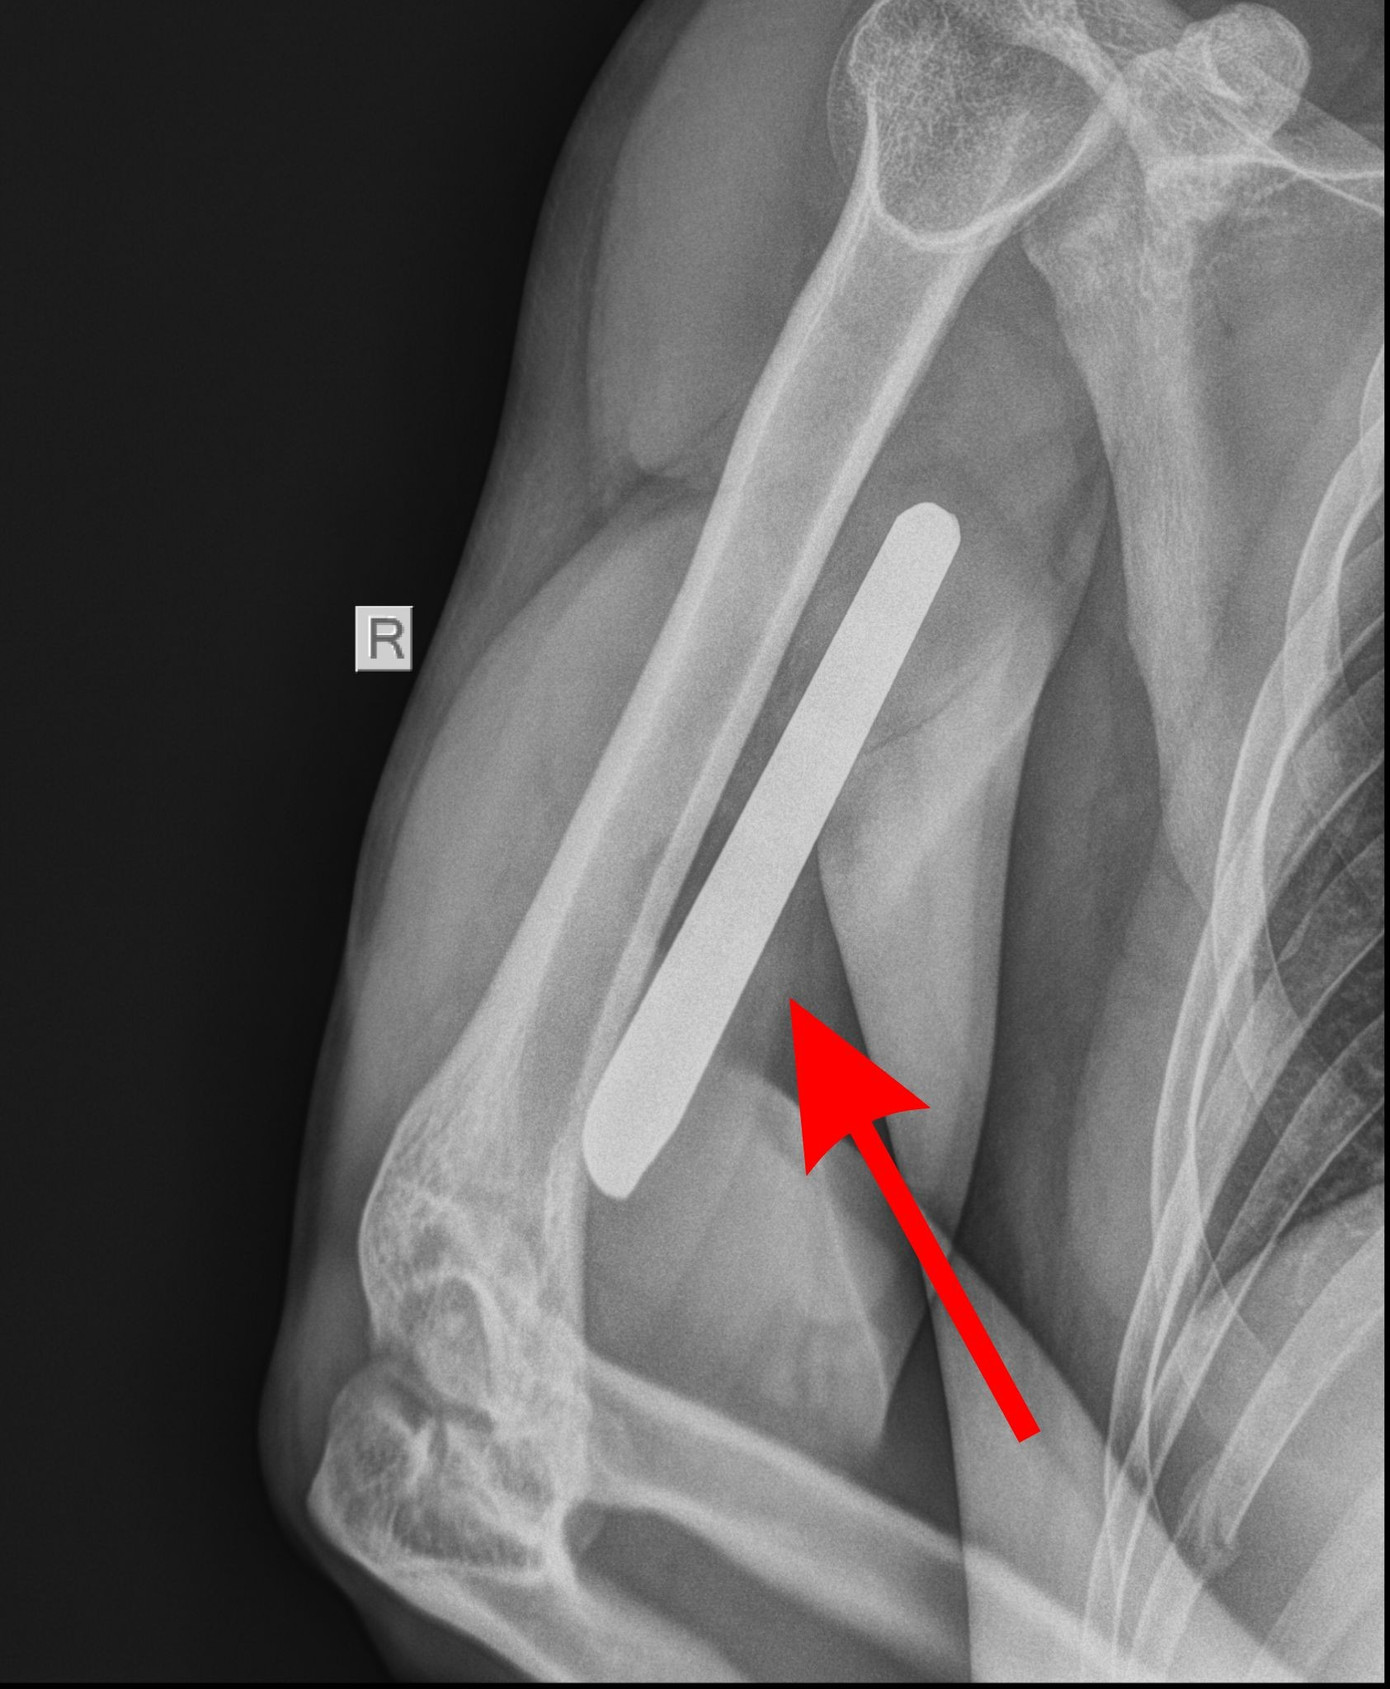

Trước đó tại tỉnh Tây Ninh, một vụ tai nạn khác xảy ra ở công trình xây dựng với mức độ rất nguy hiểm. Nạn nhân là anh T.T.B. (30 tuổi, ngụ TP.HCM), bị thanh sắt dài gần 30cm đâm xuyên cánh tay, hướng về phía lồng ngực sau cú ngã trong lúc làm việc.

Ngay sau sự cố, nạn nhân được đưa đến Bệnh viện Đa khoa Xuyên Á, TP.HCM cấp cứu. Tại đây, các bác sĩ ghi nhận dị vật đâm xuyên vùng cánh tay phải, gây hạn chế vận động, nguy cơ tổn thương đến mạch máu lớn và thần kinh.

Bệnh nhân được chỉ định phẫu thuật khẩn. Trong quá trình mổ, ê kíp phát hiện thanh sắt đã gây tổn thương phức tạp, bao gồm đứt một phần gân cơ nhị đầu, tổn thương gân cơ tam đầu, rách màng xương và lẫn nhiều dị vật trong vết thương.

Hình ảnh cây sắt đâm xuyên cánh tay nạn nhân sau cú ngã tại công trường xây dựng

Các bác sĩ tiến hành lấy dị vật, làm sạch vết thương, kiểm soát chảy máu và khâu phục hồi theo cấu trúc giải phẫu. Sau hơn một tuần điều trị tích cực, sức khỏe người bệnh dần hồi phục.